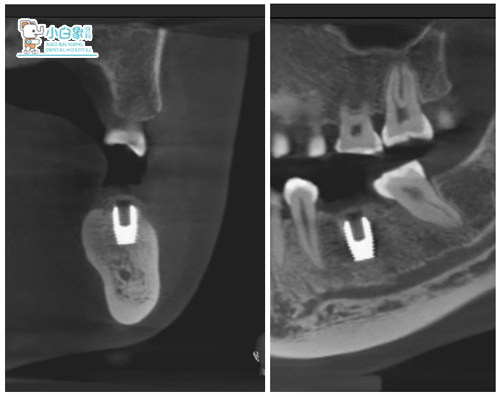

术后植入CT